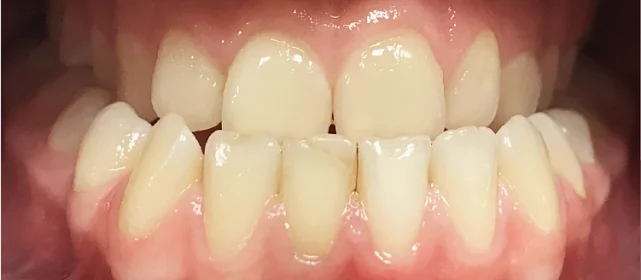

Нарушение соотношения челюстей и неправильное положение зубов — ряды смыкались некорректно, зубы стояли со смещением.

Проблема: Пациентка обратилась с жалобами на неровные зубы и неправильный прикус. Челюсти смыкались некорректно, зубы стояли со смещением. Часть зубов нуждалась в восстановлении коронками, но ставить их на кривой ряд с неправильным прикусом значит заведомо сократить им срок службы. Нагрузка будет распределяться неравномерно, и конструкции быстро выйдут из строя. Поэтому первый этап — ортодонтия, второй — протезирование.